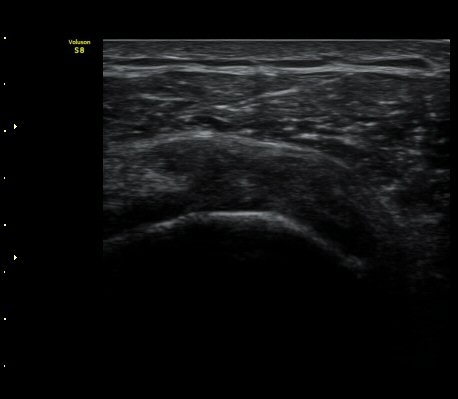

°ß°©ÇÏ±Ù°Ç »óºÎ Á¾´Ü¸é°Ë»ç»ó ¼Ò°áÀýÀÇÇÇÁú°ñÀÇ ºÒ±ÔÄ¢º¯È­¿Í °ß°©ÇÏ±Ù°Ç ¿¬°á¼º ¼Ò½ÇÀÌ

°üÂûµÊ(±×¸² 6, 7).